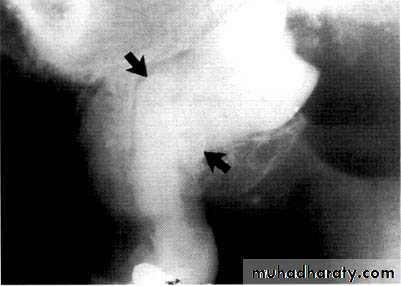

specimenX-Ray

Dilacerated root. The apical portion of the root is bent buccally or lingually into the plane of the central ray. Note the halo in the apical region, produced by the PDL

space (arrow).